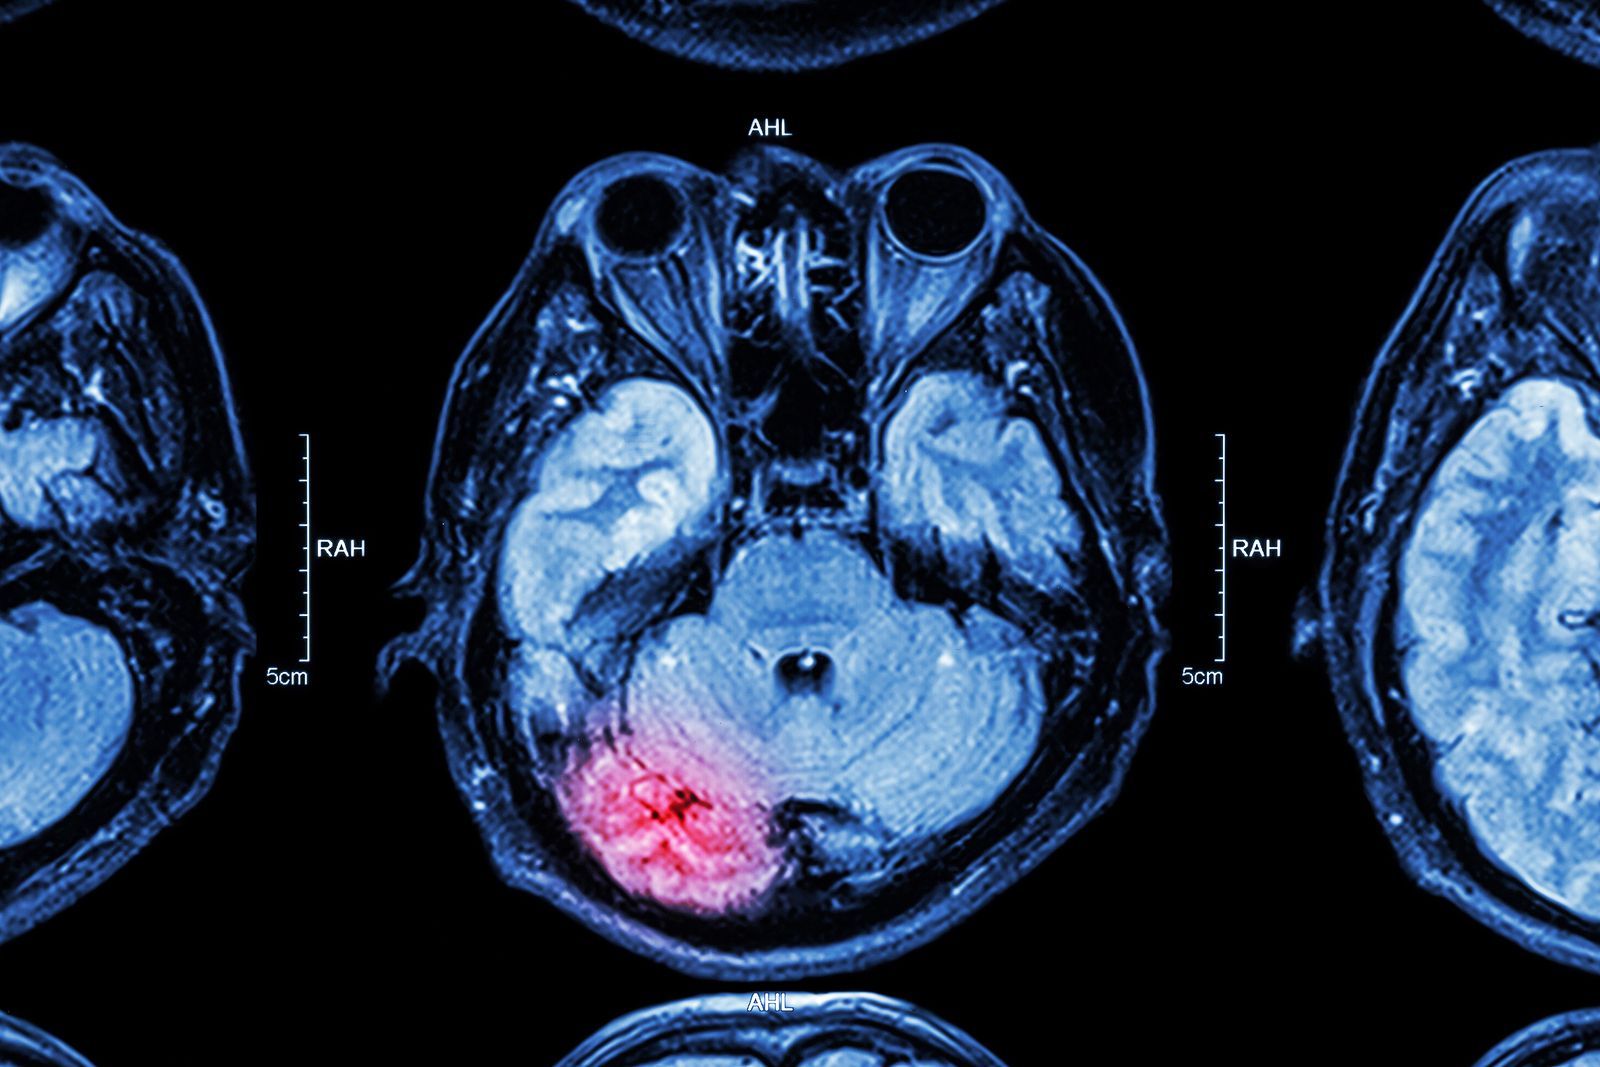

Todos sabemos que un derrame cerebral, resultado de una interrupción en el flujo sanguíneo a ambos lados del cerebro, es un suceso médico muy grave, a menudo fatal. El 20% de la población por encima de 65 años se ha visto afectada por algún accidente cerebrovascular y cada vez son más los casos entre los menores de 50 años.

"Un derrame cerebral en la parte posterior del cerebro puede causar serios problemas de equilibrio y mareos", advierte Jason Tarpley, neurólogo del Centro de Salud St. John de California. Si de verdad aparecen sin causa aparente y de forma muy repetitiva, acude de inmediato a urgencias.